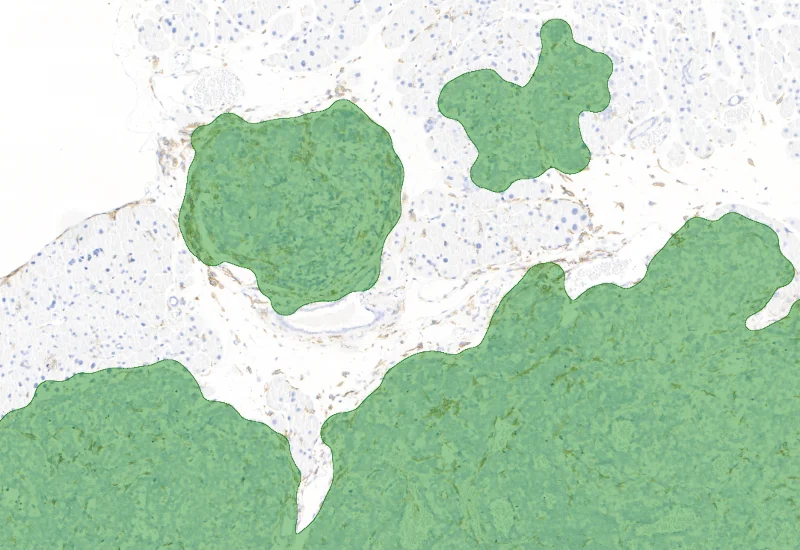

Macrophage/Tumor detection

The IHC Tumor-Macrophages APP provides tissue detection including separation into tumor tissue and healthy tissue. It detects macrophages based on a specific staining (e.g. CD68). The APP outputs the area of macrophages within tumor tissue and healthy tissue.

Segment tissue into tumor and healthy areas, detect CD68+ macrophages, and quantify macrophage area within each tissue compartment.